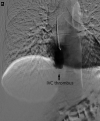

A young adult male was referred for a second opinion of deranged liver biochemistry. He initially presented two years prior with abdominal pain, lethargy and fevers due to a segment two pyogenic liver abscess. He received empirical antibiotic therapy to resolution. Computed tomography for abscess follow-up revealed an intrahepatic inferior vena cava thrombus. He was anti-coagulated with warfarin. He was lupus anticoagulant positive and had a highly positive beta-2 glycoprotein antibody on serial measurement and was diagnosed with anti-phospholipid syndrome. On current review, the patient had no clinical stigmata of chronic liver disease. There were dilated veins on the supraumbilical abdominal and chest walls. There was mild hepatomegaly but no splenomegaly. Laboratory investigations revealed mildly cholestatic liver function tests with hyperbilirubinaemia (40μmol/L) but no liver synthetic dysfunction. Serological screening did not reveal any cause of chronic liver disease. The patient underwent multiphase abdominal CT and formal hepatic venography. What is the diagnosis and describe the hepatic venous outflow?